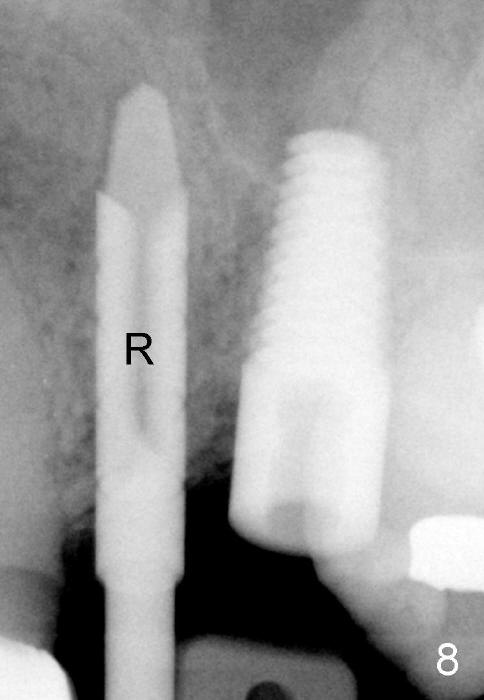

The anterior retainer is kept as a crown at #11 (Fig.2: C), whereas the residual root at the site of #13 is extracted with apical perforation (Fig.3 ^).  It is confirmed by Fig.4 (<).  To close the perforation, an osteotomy is initiated on the palatal wall of the socket with a 2 mm osteotome (Fig.5 insert: circle).  As the osteotomy is being enlarged by a 3 mm osteotome, the bone between the original socket and the osteotomy is being pushed buccally.  The former is being closed (Fig.5).  The osteotomy is finished with combination of osteotomes and reamers.  Fig.6 shows that a 5x14 mm tap is inserted at the site of #13 and that the sinus floor is lifted.  In fact the sinus membrane is partially torn at the osteotomy, which is repaired by insertion of Colla-form Dressing (Impladent), followed by autogenous bone (harvested from reamers) mixed with Osteogen  (Impladent).  A 5x14 mm implant is placed at the site of #13 with insertion torque more than 60 Ncm (Fig.7: I).  An incision is made at the site of #12 to start osteotomy with insertion of a parallel pin (Fig.7 P).  A 3 mm reamer is kept in place for position confirmation (Fig.8 R).  Due to ridge atrophy (Fig.2 arrowheads), a much smaller, but longer implant is placed at the site of #12 (Fig.9: 4x17 mm).  The autogenous bone harvested from #12 osteotomy is placed in the buccal gap of #13, followed by insertion of Colla-form Dressing (Fig.10 M).  To protect the membrane, a short abutment (4x3 mm) is temporarily placed (Fig.9,10 A) and perio dressing (Fig.9 D) is applied around the abutment and the interproximal areas of the neighboring teeth.  Usually perio dressing dislodges around 1 week postop, particularly for a large edentulous space.  In this case, the dressing is quite stable 11 days postop: the abutment (Fig.11 A) appears to contribute to retention of the dressing (D).